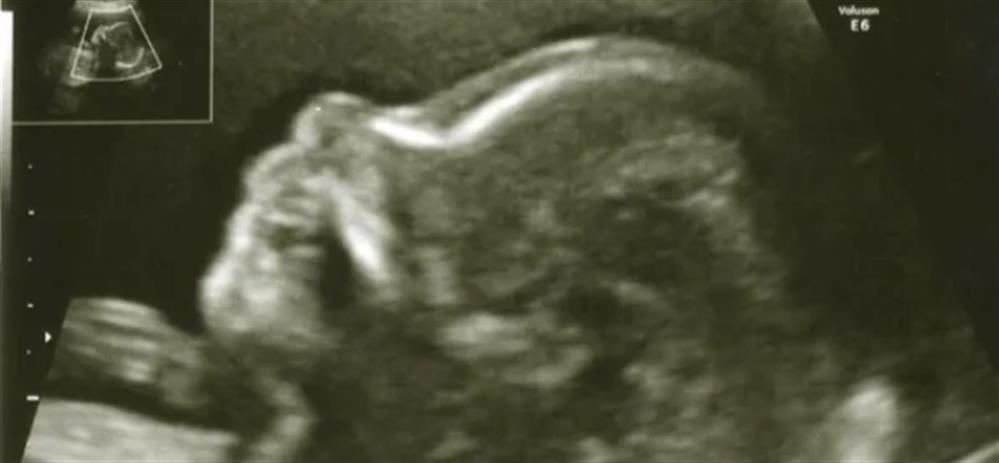

Η εξέταση του Β επιπέδου είναι μια λεπτομερής εξέταση της ανατομίας του εμβρύου, το οποίο εκτελείται στο δεύτερο τρίμηνο της εγκυμοσύνης, μεταξύ 20-24 εβδομάδες της κυήσεως.

Κατά τη διάρκεια αυτού του υπερηχογραφήματος εξετάζεται αναλυτικά κάθε μέρος του σώματος του εμβρύου, προσδιορίζεται η θέση του πλακούντα, η ποσότητα του αμνιακού υγρού και γίνονται μετρήσεις της ανάπτυξης του εμβρύου. Επίσης, μετράται το μήκος του τραχήλου της μήτρας της εγκύου και η ροή του αίματος στις μητριαίες αρτηρίες που τροφοδοτούν τη μήτρα και τον πλακούντα, ώστε να προσδιοριστεί ο κίνδυνος προεκλαμψίας και πρόωρου τοκετού. Η εξέταση στο ΜΗΤΕΡΑ διενεργείται σύμφωνα με τις «Κατευθυντήριες οδηγίες υπερηχογραφικού ελέγχου στην Μαιευτική- Υπερηχογράφημα 2ου τριμήνου της κύησης» της Ελληνικής Εταιρίας Υπερήχων στη Μαιευτική & Γυναικολογία.

Συμπερασματικά, το υπερηχογράφημα β-επιπέδου είναι η πιο σημαντική και αναλυτική εξέταση του εμβρύου και συστήνεται να γίνεται από όλες τις εγκύους.